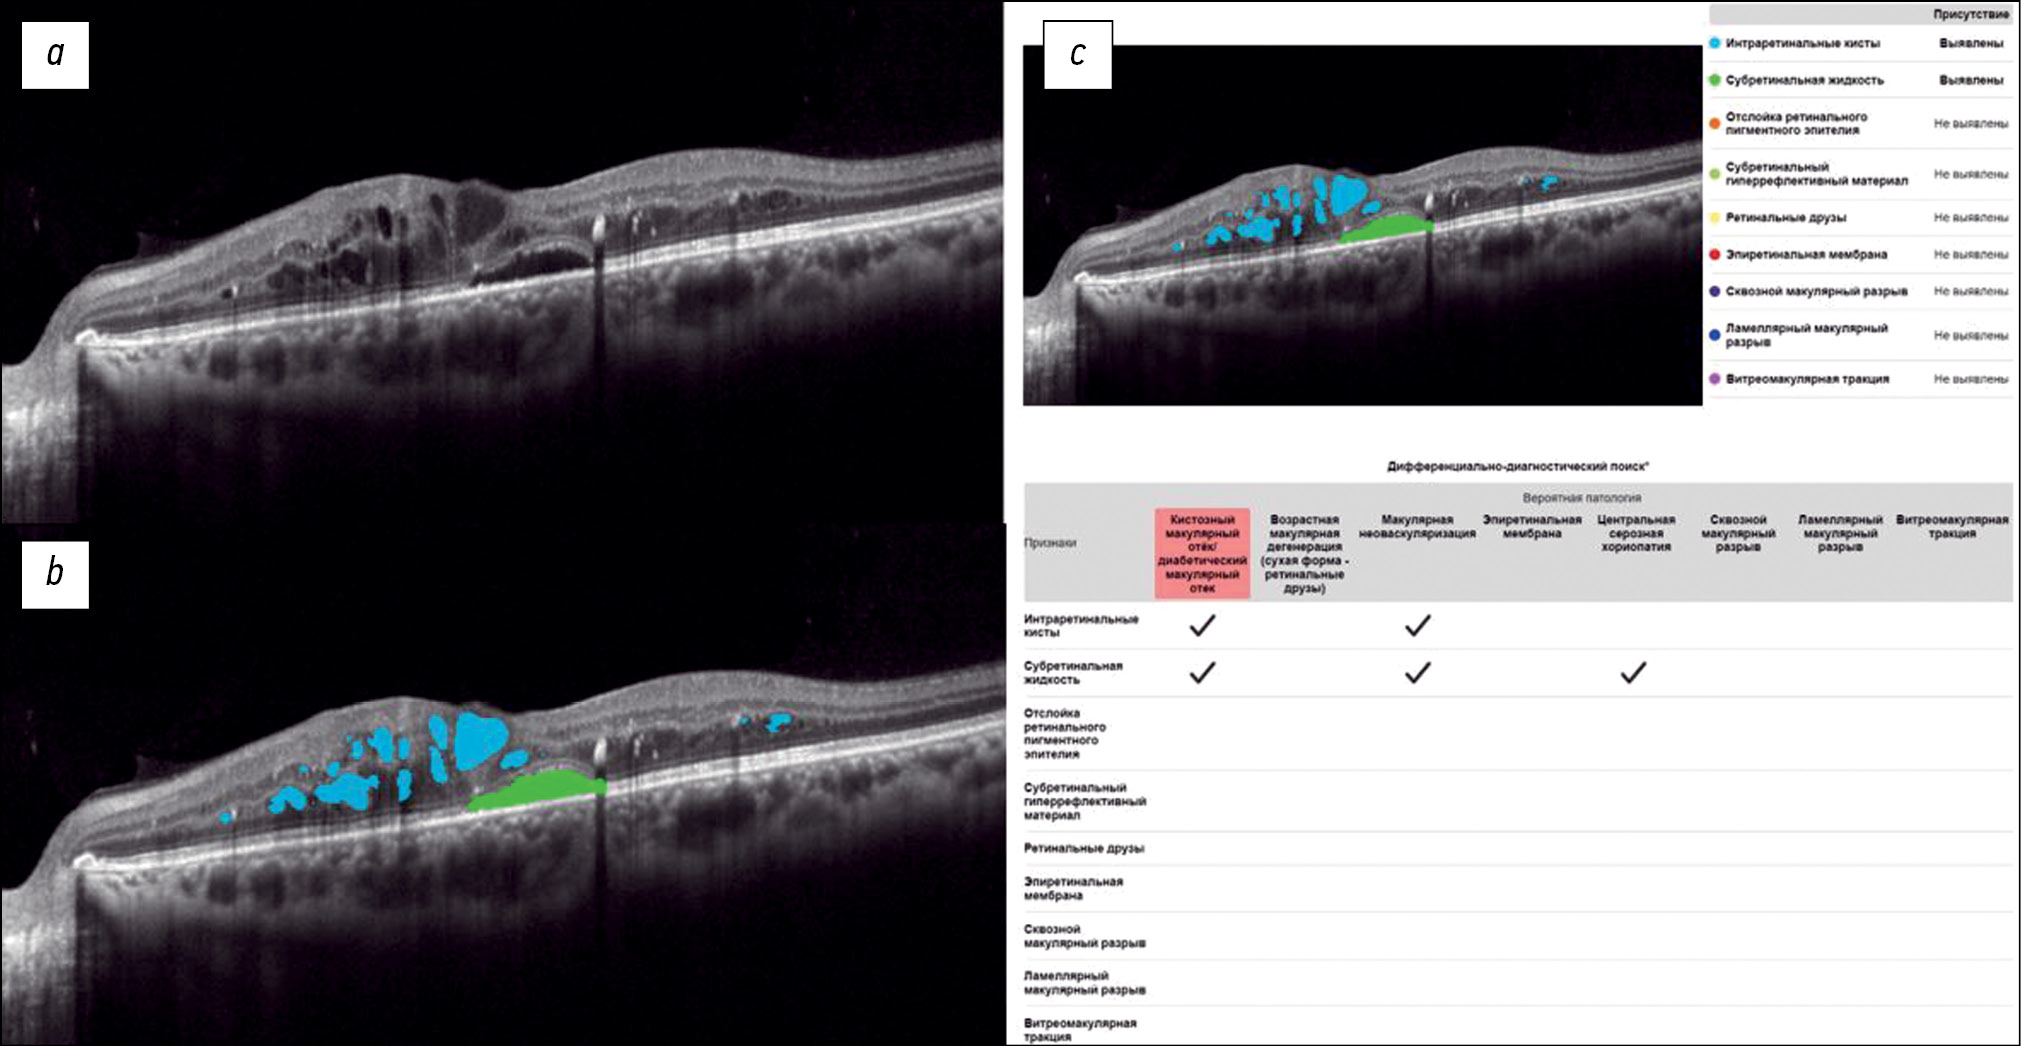

Exploring the possibilities of an artificial intelligence program in the diagnosis of macular diseases

Resumo

BACKGROUND: Macular diseases are a large group of pathological conditions that cause vision loss and visual impairment. Early diagnosis of such changes plays an important role in treatment selection and is one of the crucial factors in predicting outcomes.

AIM: To examine the potential of an artificial intelligence program in the diagnosis of macular diseases using structural optical coherence tomography scans.

MATERIALS AND METHODS: The study included patients examined and treated at the Federal Research and Clinical Center of Specialized Medical Care and Medical Technologies and Moscow Regional Research and Clinical Institute. In total, 200 eyes with macular diseases were examined, as well as eyes without macular pathologies. A comparative clinical analysis of structural optical coherence tomography scans obtained using an RTVue XR 110-2 tomograph was conducted. The Retina.AI software was used to analyze optical coherence tomography scans.

RESULTS: In the analysis of optical coherence tomography scans using Retina.AI, various pathological structures of the macula were identified, and a probable pathology was then determined. The results were compared with the diagnoses made by ophthalmologists. The sensitivity, specificity, and accuracy of the method were 95.16%, 97.76%, and 97.38%, respectively.

CONCLUSION: Retina.AI allows ophthalmologists to automatically analyze optical coherence tomography scans and identify various pathological conditions of the fundus.